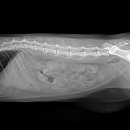

24시 다산 원동물의료센터 남양주 다산동물병원 24시 강아지건강검진 글,사진 / ⓒ나나로그 반려견과... 대학병원급 CT영샹센터도 준비되어있다고하는데 정밀 검사가 필요하면 외부로 이동할 필요 없이 바로...

남양주 다산동물병원 24시 고양이건강검진 후기 신장검사 원동물의료센터 경기 남양주시 다산중앙로 15... 24시 동물병원에서 고양이 건강검진을 하고온 후기를 소개해드릴게요. ⏰ 영업시간: 24시 주차 ⭕ 병원...

이후에 병원에서 전화가 와서 아이를 데릴러 오면 되더라고요 특히 담당쌤이 검사결과를 보면서 건강상태와 주의 할점? 등등 자세히 설명해 주셨어요 남양주 다산동물병원 24시 고양이건강검진 베이직 검사...

남양주 다산동물병원 24시 원동물의료센터에서는 정말 다양한 진료, 수술을 받을 수 있어요. 특히 노묘,노견들은 위급시 바로 안아서 뛰어가서 진료 받을 수 있는 병원으로 다녀야하잖아요. 그리고 모든...